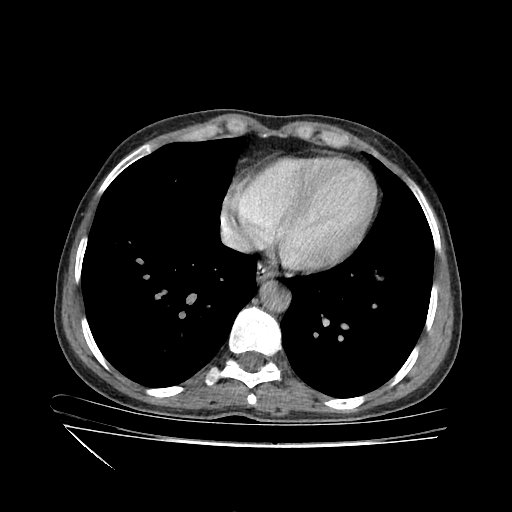

Original VENOUS CT scan

Full window (WL 1023.5, WW 4095 β†’ Low βˆ’1024, High +3071)

Lung window (WL -600, WW 1500 β†’ Low βˆ’1350, High +150)

Mediastinum window (WL 40, WW 400 β†’ Low βˆ’160, High +240)